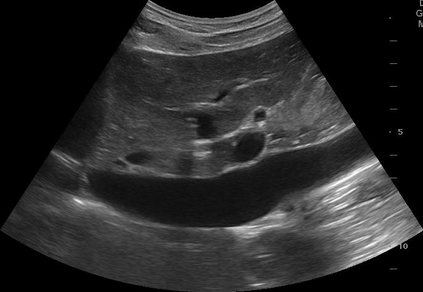

Most deep neural networks (DNNs) based ultrasound (US) medical image analysis models use pretrained backbones (e.g., ImageNet) for better model generalization. However, the domain gap between natural and medical images causes an inevitable performance bottleneck. To alleviate this problem, an US dataset named US-4 is constructed for direct pretraining on the same domain. It contains over 23,000 images from four US video sub-datasets. To learn robust features from US-4, we propose an US semi-supervised contrastive learning method, named USCL, for pretraining. In order to avoid high similarities between negative pairs as well as mine abundant visual features from limited US videos, USCL adopts a sample pair generation method to enrich the feature involved in a single step of contrastive optimization. Extensive experiments on several downstream tasks show the superiority of USCL pretraining against ImageNet pretraining and other state-of-the-art (SOTA) pretraining approaches. In particular, USCL pretrained backbone achieves fine-tuning accuracy of over 94% on POCUS dataset, which is 10% higher than 84% of the ImageNet pretrained model. The source codes of this work are available at https://github.com/983632847/USCL.